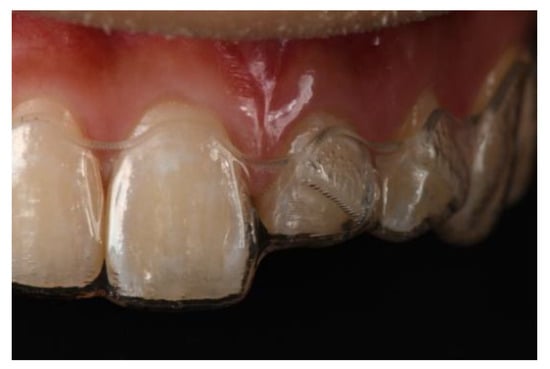

2.1. Ferrule/Crown Lengthening

5. Conclusions